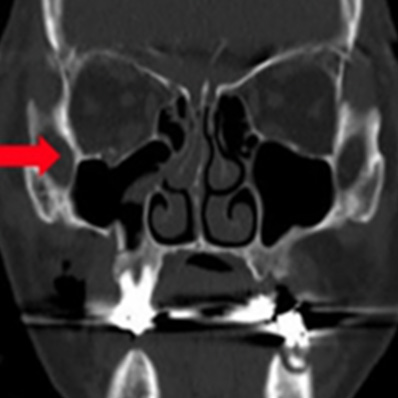

眼窩底骨折